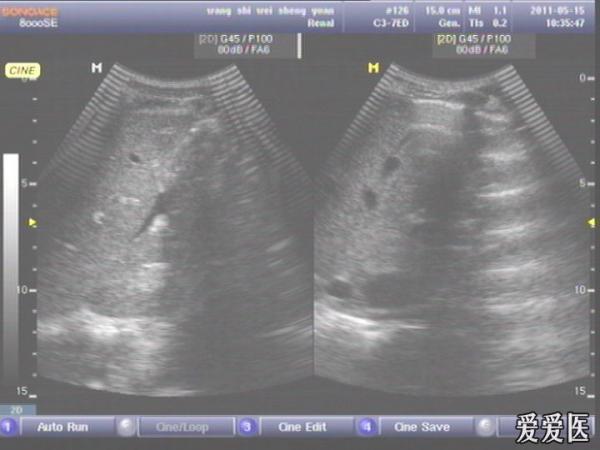

患者,男,38岁,进食后突发上腹部持续性剧烈疼痛一小时来查。超声见横膈与肝之间、上腹部皮下气体强反射回声,后伴多重反射,肝前、肝肾间隙,腹腔肠管间均可见游离无回声区。直视腹部见上腹部似板样。结合病史提示“胃肠道穿孔”。急诊手术证实。